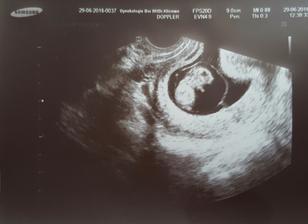

Gratuluji, je to veliký zázrak!!🙂 Z ničeho je malý tvoříček!! 🙂 už se těšíme na druhé,l ale ješte si poškáme, termín máme 01.01.2017